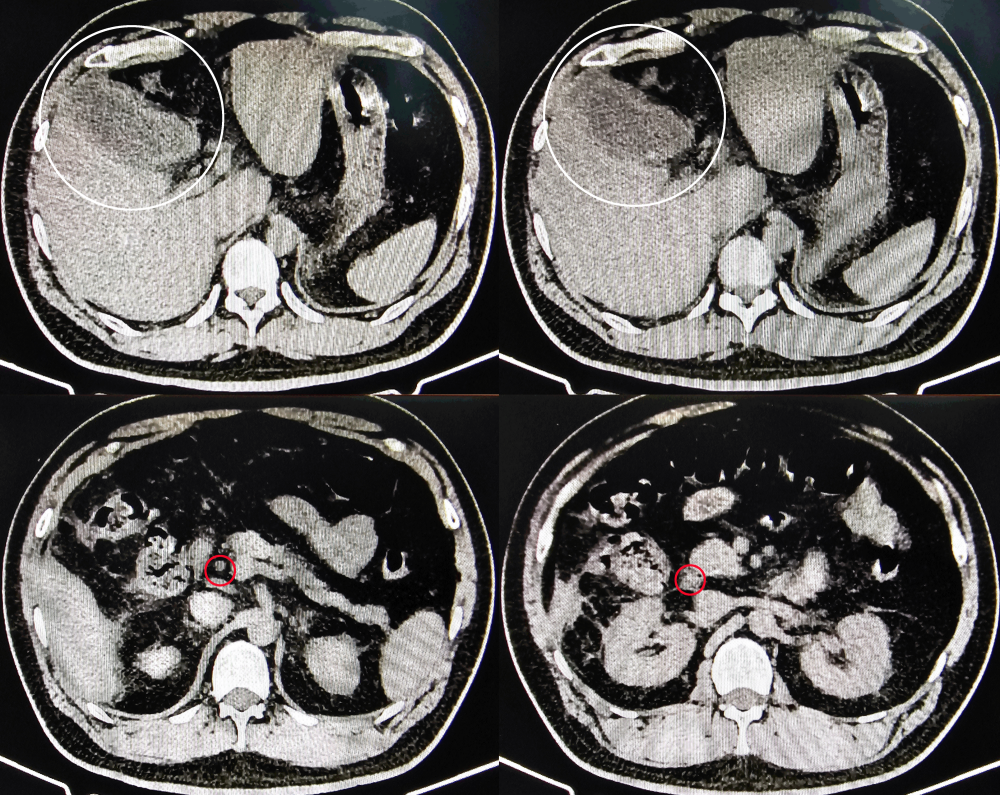

综合患者信息,得出以下结论:患者休克指数为1.13,处于轻度休克状态,临床表现符合Charcot三联征(腹痛、黄疸、寒战高热);辅助检查显示腹部CT可见胆总管结石及胆囊炎表现;确诊为胆囊结石伴急性胆囊炎、胆总管结石伴急性胆管炎。虽未构成Reynolds五联征,但考虑存在随时发展为急性化脓性胆管炎的风险。决定立即实施补充血容量、抗感染及解痉治疗,并尽快安排急诊手术。

经过两小时紧急救治,患者生命体征暂趋平稳。利用这一窗口期,迅速转至手术室进行急诊手术。术中发现胆囊化脓、坏疽,胆总管内充满脓液。胆道镜探查见胆总管末端结石。遂行胆囊切除、胆总管取石及T管引流术。